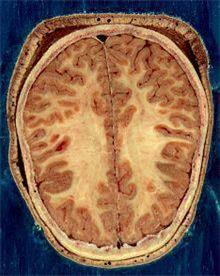

대뇌는 신경 세포체로 구성된 겉 부분인 피질과 신경세포들을 서로 연결하는 신경 섬유망이 깔린 속 부분인 수질로 이루어져 있다. 피질은 회색을 띠고 있어 회색질, 수질은 하얀색을 띠고 있어 백질이라고 불린다.

뇌 MRI 스캔에서는 흡입용 스테로이드와 전신 스테로이드(주사 또는 정제) 사용자가 모두 스테로이드를 사용하지 않는 사람들보다 백질의 구조가 온전하지 못한(less intact) 것으로 나타났다.

백질 구조의 불완전성은 흡입용 스테로이드 사용자보다 전신 스테로이드 사용자가 더 심했다고 연구팀은 밝혔다.

또 어떤 스테로이드든 오래 사용한 사람일수록 백질 구조 이상이 심했다.

회색질에서는 스테로이드 사용자가 미상핵(尾狀核: caudate nucleus)과 편도체(扁桃體: amygdala) 구조가 온전하지 못한 것으로 나타났다.

전신 스테로이드 사용자는 스테로이드를 사용하지 않는 사람보다 미상핵이 크고 흡입용 스테로이드 사용자는 편도체가 작았다.

미상핵과 편도체는 모두 뇌의 회색질에서 인지와 감정 조절을 담당하는 부위들이다.